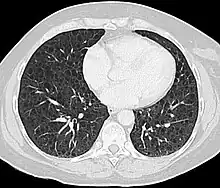

CT scan of the lungs in a patient with lymphangioleiomyomatosis showing numerous thin walled cysts within the lungs

LAM can come to medical attention in several ways, most of which trigger a chest CT. Thin-walled cystic change in the lungs may be found incidentally on CT scans of the heart, chest or abdomen (on the cuts that include lung bases) obtained for other purposes. HRCTs of TSC patients reveals that about 20% of women have cystic change by age 20 and about 80% of women have cystic changes after age 40.[80] LAM is sometimes revealed by chest CT in patients who present with an apparent primary spontaneous pneumothorax, but more often CT scanning is not ordered (in the United States) until recurrences occur. Progressive dyspnea on exertion without the exacerbations and remissions that are characteristic of asthma or COPD sometimes prompt a chest CT. A review of the CT by an expert familiar with LAM may increase diagnostic accuracy.[81] Chylothorax can also bring LAM to attention.

The high-resolution computed tomography (HRCT) chest scan is better than the chest radiograph to detect cystic parenchymal disease and is almost always abnormal at the time of diagnosis, even when the chest radiograph and pulmonary function assessments are normal.[4][6][7][88] The typical CT shows diffuse round, bilateral, thin-walled cysts of varying sizes ranging from 1 to 45 mm in diameter.[6][7] The numbers of cysts varies in LAM from a few to almost complete replacement of normal lung tissue. The profusion of cysts tends to be milder in patients with TSC-LAM than S-LAM, perhaps explained in part because TSC-LAM patients typically receive earlier screening.[12] Pleural effusions are seen on CT in 12% of patients with S-LAM and 6% of patients with TSC-LAM. Other CT features include linear densities (29%), hilar or mediastinal lymphadenopathy (9%), pneumothorax, lymphangiomyoma, and thoracic duct dilation.[6][7] Ground-glass opacities (12%) suggest the presence of interstitial edema due to lymphatic congestion. In patients with TSC, nodular densities on HRCT may represent multifocal micronodular pneumocyte hyperplasia (MMPH) made up of clusters of hyperplastic type II pneumocytes.[80][89][90] MMPH may be present in males or females with TSC in the presence or absence of LAM, but not in patients with S-LAM.[91] MMPH is not typically associated with physiologic or prognostic consequences, but one case of respiratory failure due to MMPH has been reported.[92][93][94]